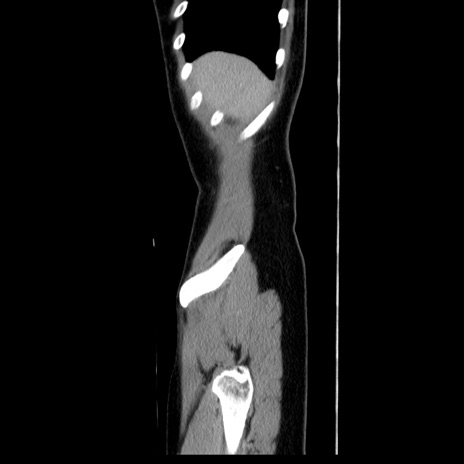

症例39(矢状断像)

【症例】40歳代女性

【主訴】上下腹部痛

【現病歴】2日目から下腹部痛あり。夜間は痛みで眠れなかった。昨日より上腹部痛と下痢が出現。臥位で痛みは軽快したため、休んでいた。本日になって臥位でも立位でも痛みが強くなってきたため救急要請。

【既往歴】子宮内膜症

【身体所見】部:平坦・軟、左上下腹部に圧痛あり、反跳痛あり。

【データ】WBC 21800、CRP 26.78

CT